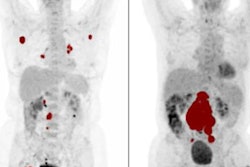

FDG-PET images are from a 12-year-old male diagnosed with clinical stage II non-Hodgkin's lymphoma. Staging PET image (left) shows no lymphoma lesions outside the regular field-of-view. Interim PET image (right) shows a complete metabolic response after two cycles of chemotherapy. Patient was disease-free at 12-month follow-up. Images courtesy of JNM."Our evidence reinforces that regular field-of-view PET/CT is sufficient in pediatric lymphoma, both at staging and interim assessments," the researchers concluded, adding that the findings do not suggest a routine field-of-view approach is applicable to other pediatric tumors.